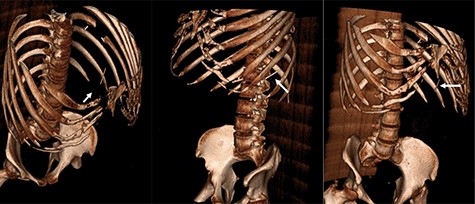

Three-dimensional reconstruction CT scan displaying the foreign body (white arrow) in three different orientations.